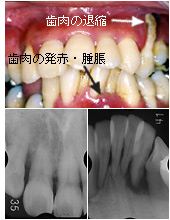

症例1:中等度歯周炎患者の治療例

- 患者

- 45歳、男性

- 診断

- 成人性歯周炎

- 所見

- 前歯部では、歯間が離開しており、唇側傾斜がある。全顎的に歯肉の炎症も著明である。レントゲンでは、全顎的に根の1/2程度の骨吸収がある。また一部には垂直性の骨吸収があり、第一大臼歯部は、根尖部まで吸収している部位もある。

- 治療方針

- 細菌の機械的除去を行うとともに,口腔清掃指導を行い再感染を予防する。同時に局所因子にも対応するとともに,歯周外科処置を行い,患者が細菌をコントロールしやすく,また再感染しにくい環境をつくる。

- 治療計画

- 歯周初期治療(TBI、SRP)

歯周外科処置(人工骨移植、GTR法等含む)

(上下顎左右臼歯部、上顎前歯部)

MTM(上下顎前歯部)

メインテナンス(SPT)

歯周治療を行うことによって、初診時にあった歯肉の発赤・腫脹はなくなりました。レントゲンにおいても、初診時は骨梁が不明瞭だったのが、はっきりとしてきました。治療が終了して、定期的なメインテナンスを行い始めて10年以上が経過していますが、現在でも特に大きな問題を起こすことなく良好な経過をたどっています。